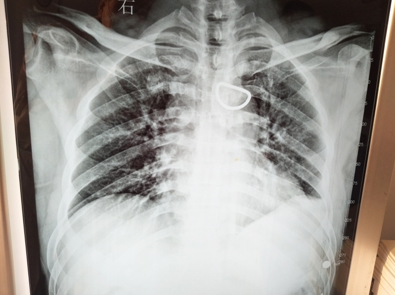

左锁骨对位对线、左肩胛后中线5、6、7肋骨对位对线。(复位后)